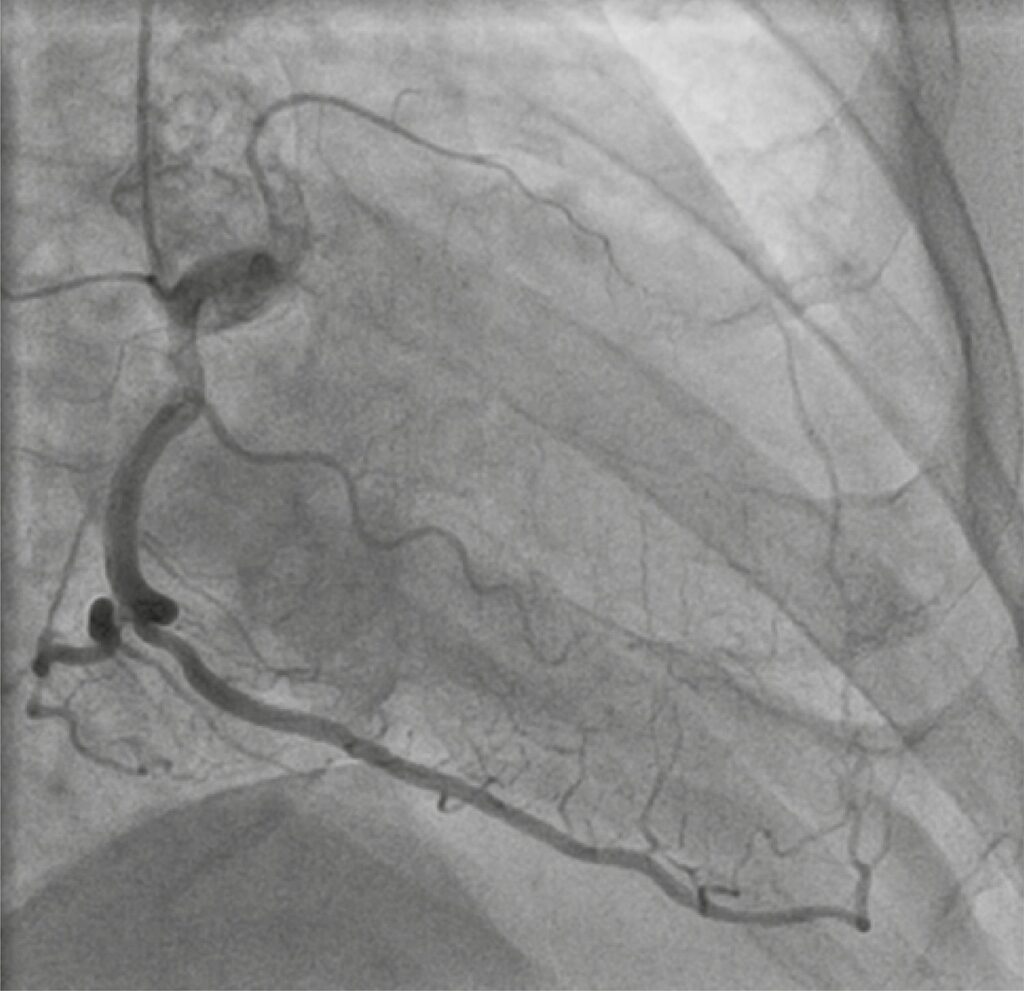

Um homem de 67 anos com vários fatores de risco cardiovascular foi encaminhado para consulta cardiológica, devido à angina de esforço classe II/IV da classificação da Canadian Cardiology Society (CCS), nos últimos 6 meses, em terapia medicamentosa otimizada. O eletrocardiograma de repouso e o ecocardiograma transtorácico (ETT) estavam normais. O teste de esforço em esteira foi positivo. A angiografia coronária revelou uma oclusão total crônica (OTC) proximal longa da artéria descendente anterior (DA; J-CTO=1, Rentrop3), OTC distal da artéria circunflexa (J-CTO=0, Rentrop3) e estenose de 50% no ramo posterolateral (escore SYNTAX 21).

Levando em consideração os sintomas, os resultados angiográficos e a preferência do paciente, planejou-se intervenção coronária percutânea (ICP) da DA, como prioridade, que foi realizada com uso de acesso birradial, injeção contralateral e abordagem anterógrada com escalonamento de fios ( ). Um fio-guia Sion foi avançado até a DA distal, com a ajuda de um microcateter FineCross . Dois stents farmacológicos sobrepostos com everolimus (2,5x48mm e 3x23mm) foram implantados na DA proximal, após a devida pré-dilatação. Imediatamente após a pós-dilatação com balão não complacente (3x23mm) em 22atm, o paciente desenvolveu uma perfuração grave do tipo Ellis III no segmento médio da DA (). O balão da pós-dilatação foi insuflado novamente a 8atm no local da perfuração, para estancar o sangramento. Foi realizado um ETT à beira do leito, que revelou pequeno derrame pericárdico circunferencial sem impacto hemodinâmico.